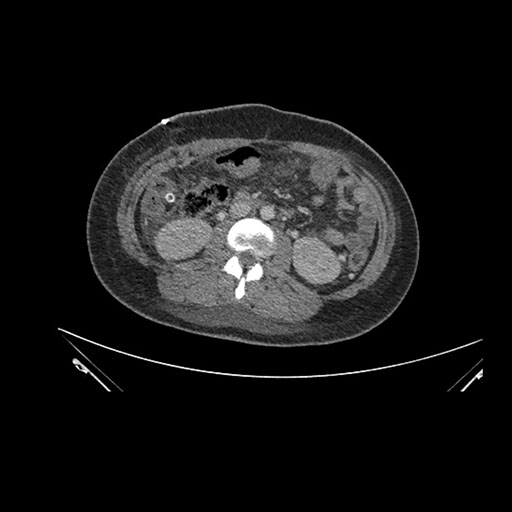

Imaging Analysis

Look through the patient's CT scan to identify any areas of concern for the necessary procedure.

Axial Arterial

Based on initial findings, which issue(s) would you be most concerned about?